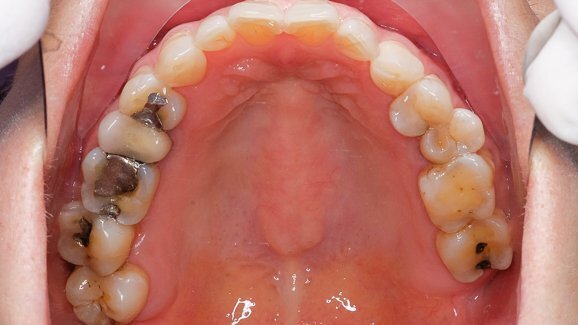

Gli studi dovranno adottare dei separatori e sarà loro proibito di effettuare il lavaggio degli scarti di amalgama (ad esempio i filtri) scaricando nelle condutture. Il regolamento vieta inoltre l’uso di candeggina o detergenti contenenti cloro perché potrebbero provocare lo scioglimento del mercurio solido durante la pulizia del riunito.

Anche se dall’odontoiatria proviene meno dell’1% di mercurio rilasciato nell’ambiente da fonti artificiali, l’ADA ha esortato gli studi dentistici a far proprie le pratiche di gestione ottimale di tali scarti. Nel 2009, l’Associazione si prese cura di modificarle perché incluse l’uso di separatori di amalgama conformi allo standard ANSI/ADA n. 108 traendo spunto dalle norme elaborate dall’International Organization for Standardization, ossia la Federazione mondiale degli organismi nazionali di normalizzazione.

Esentati dalla nuova regola sono i dentisti che praticano la patologia orale, la radiologia orale e maxillo-facciale, la chirurgia orale e maxillo-facciale, l’ortodonzia, la parodontologia e la riabilitazione protesica. Esenta inoltre anche quelli che non posizionano amalgama e che la rimuovono solo in situazioni impreviste o di emergenza (presumibilmente sono meno del 5 per cento di tutte le rimozioni) e sulle unità dentali mobili. Dentisti che hanno già separatori sono esentati per dieci anni.

L’EPA prevede che la conformità alla normativa potrà ridurre annualmente gli scarti annuali di mercurio di 5,1 tonnellate e di 5,3 tonnellate di altri metalli presenti negli impianti di trattamento di proprietà pubblica.